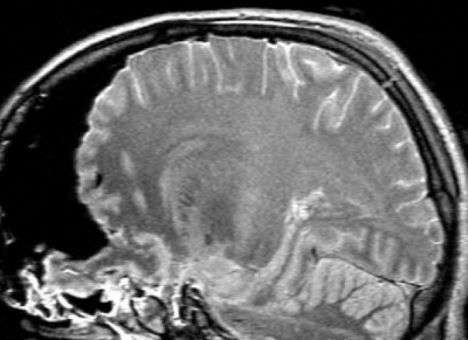

"Операция уже не имела на том этапе смысла, я не считал разумным продолжение лечения. Пациент был фактически мертв, это была смерть мозга", — рассказал нейрохирург.